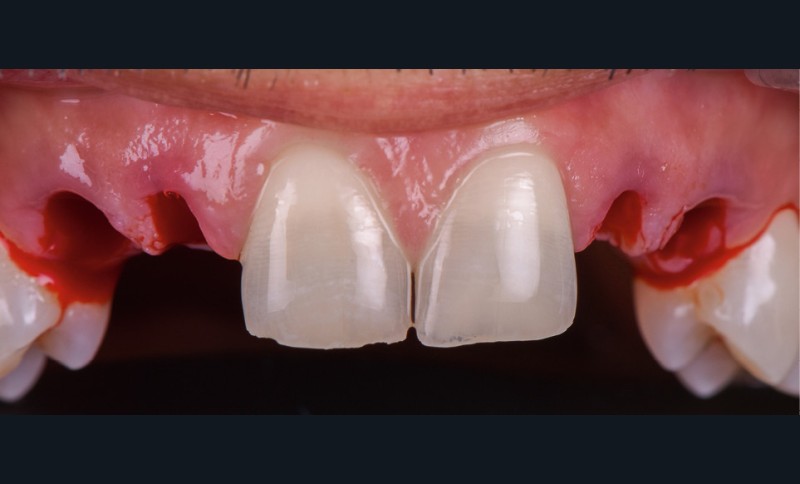

- extraction des dents 52 53 62 63 de manière « atraumatique » (fig. 3) ;